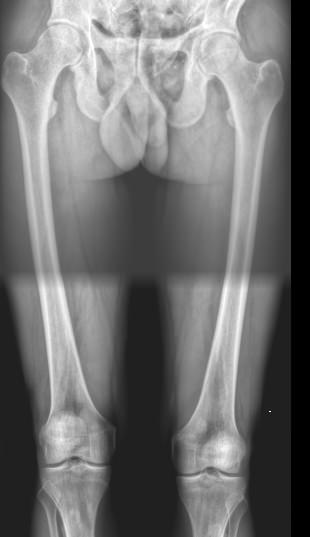

Рентгеновское исследование ― первичный вид диагностики, который назначают при переломах и подозрении на патологию костной ткани. Это неинвазивная, широко доступная и высокоинформативная процедура, во время которой пациент не испытывает никаких ощущений. Полную информацию о состоянии обследуемого участка тела можно получить уже через 10 минут после обследования. При этом современные рентгеновские аппараты излучают минимум ионизирующего излучения, позволяющие безопасно делать множество снимков в год, например, для контроля и коррекции проведенного лечения.

Рентгенограмма необходима хирургу, травматологу или ортопеду для подтверждения или исключения следующей патологии:

• Перелом;

• Остеомиелит и другие воспалительные процессы;

• Патологии мягких тканей;

• Новообразование или метастазирование.

Что показывает рентген обеих бедренных костей в одной проекции

• Травматические повреждения одной или обеих костей ― место перелома, осколки;

• Участки изменений костной ткани, такие как воспаление, гнойное или асептическое, разрежение, размягчение, склерозирование или новообразования;

• Участки поражения мягких тканей, например, кисты, другие новообразования или миозиты, протекающие с оссификацией мышцы.